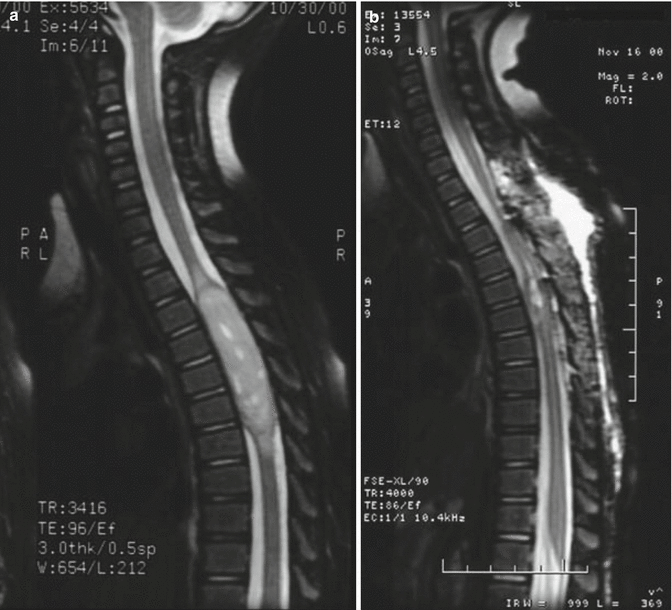

髓内脊髓肿瘤(IMSCTs),如下图所示,是指硬膜内脊髓肿瘤的一个亚群,由脊髓内的细胞产生,与相邻结构如神经根或脑膜相对。它们比脑瘤少见得多,据认为占中枢神经系统全部固有肿瘤的5-10%。他们常见的初始症状是全身性背痛,临床上很难将背痛与肌肉骨骼疾病区分开来。大多数髓内肿瘤被认为是起源于胶质细胞,因为它们在组织学和免疫组织化学上类似于分化的非神经元细胞类型,如室管膜细胞和星形胶质细胞,它们出现在非病理的脊髓组织中。由于许多此类肿瘤生长缓慢,诊断前症状平均为2年。恶性或转移性脊髓肿瘤患者在症状出现后几周到几个月出现。

常见的髓内肿瘤是室管膜瘤、星形细胞瘤和血管母细胞瘤。总的来说,脊髓室管膜瘤和星形细胞瘤占髓内肿瘤的80-90%,其中室管膜瘤的发生频率大约是星形细胞瘤的两倍。在成人中,室管膜瘤是常见的瘤种。在儿童中,星形细胞瘤是常见的瘤种,